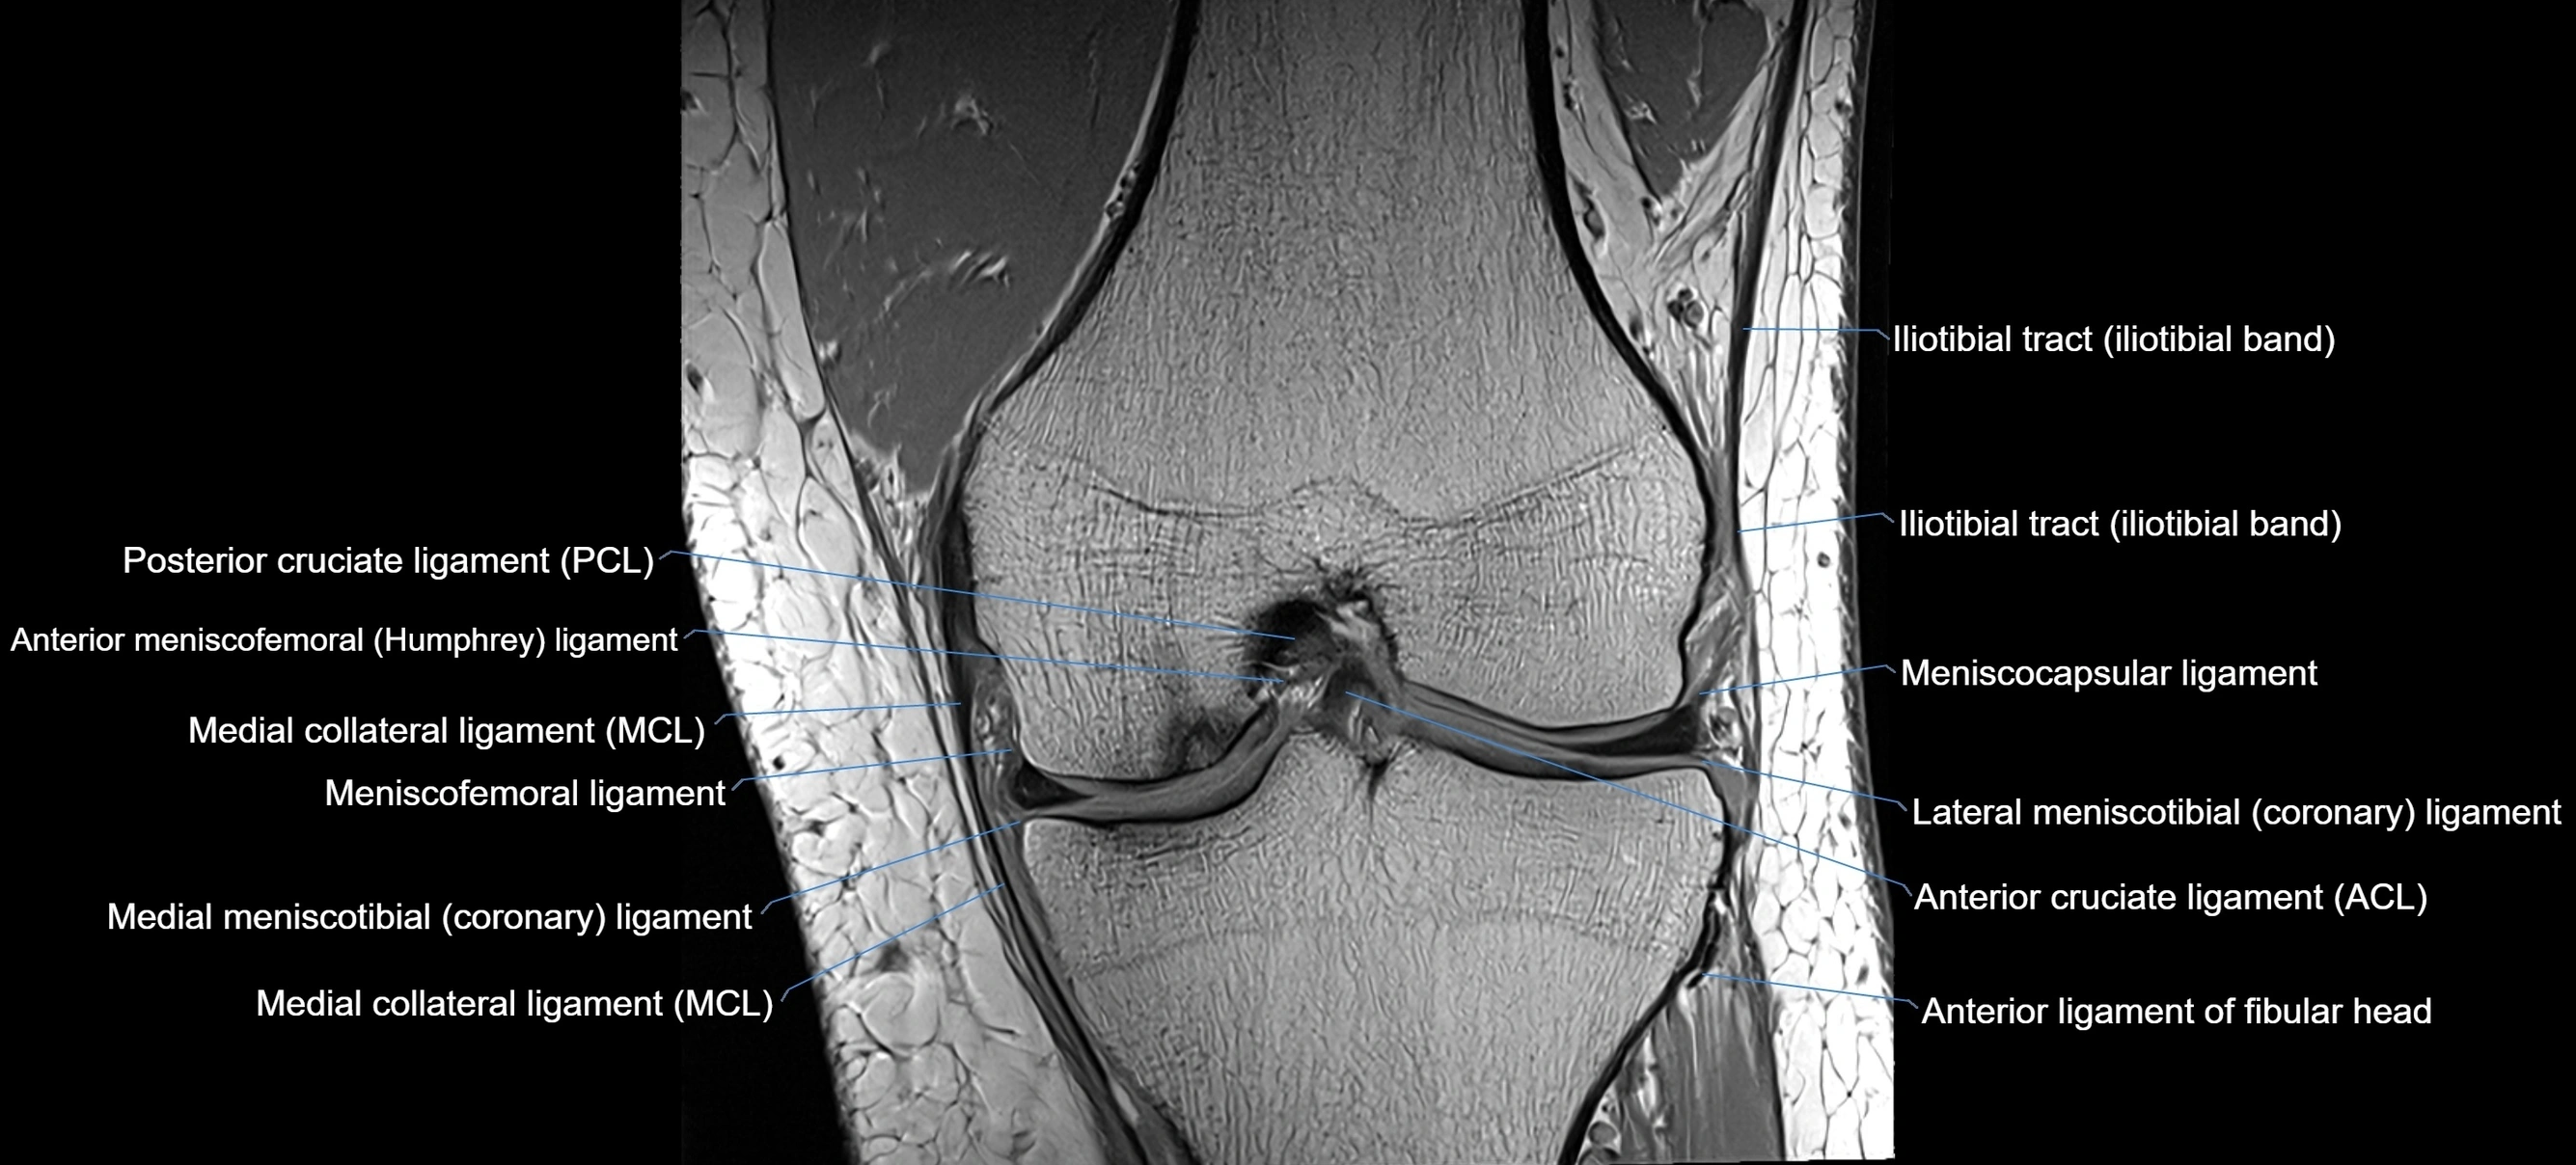

MRI Appearance

T1-weighted images:

• Normal ACL appears as a low-signal band-like structure crossing the intercondylar notch

• Surrounded by intermediate signal synovial fluid and fat planes

T2-weighted images:

• Normal ACL remains low signal

• Partial or complete tears appear as discontinuity, increased signal, or fiber laxity

MRI images

image